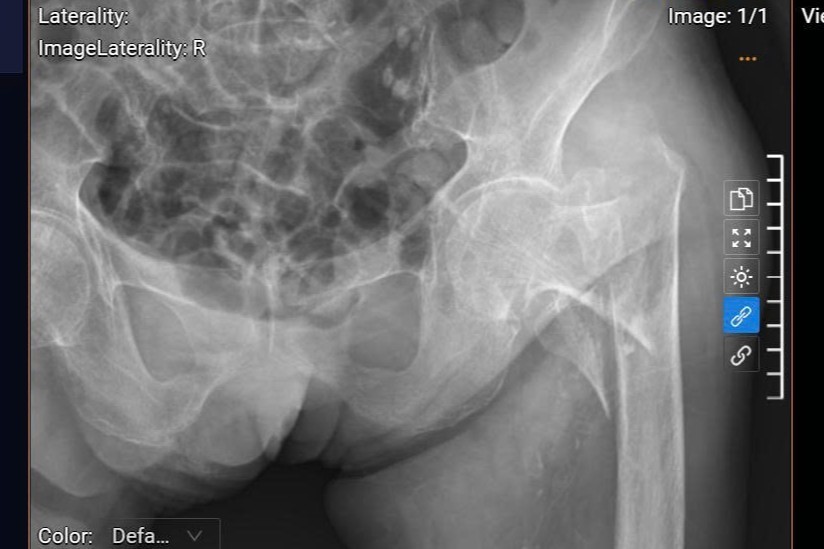

Phim chụp X Quang của bệnh nhân Vũ Thị K, 93 tuổi ở TP. Hải Phòng bị gãy cổ xương đùi trái